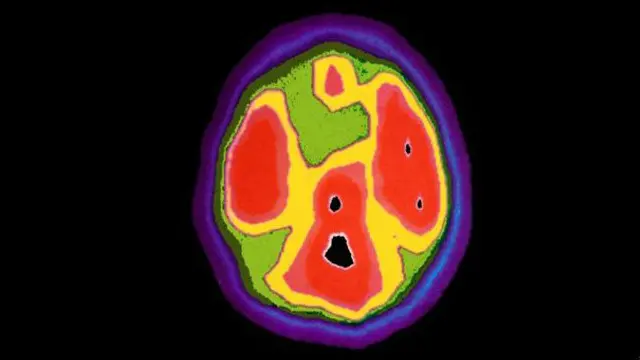

Автор фото, SPL